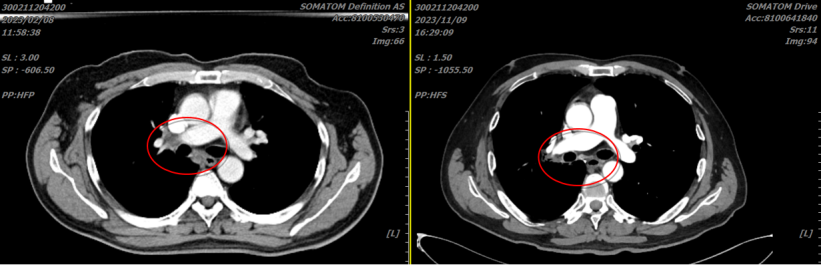

病例二:杨某某,男,62岁,诊断:1.小细胞肺癌;cT4N2M0 III期;KPS评分:90分;2.直肠恶性肿瘤个人史;3.左束支传导阻滞;4.2型糖尿病。于2023-02-14行肺部重(碳)离子放疗。并行光子全脑预防照射。截至2026年3月,治疗后37个月,患者状况良好。下图为治疗前和治疗后9个月对比较长。红圈内为肺门原发肿瘤和转移性淋巴结治疗前后的变化。

【病例提供医生:马彤 科室:放疗中心一科(国际一部)】